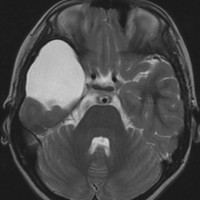

シルビウス裂くも膜のう胞,中頭蓋窩くも膜のう胞

最も多いタイプで50%くらいです。7歳の子に偶然発見された右シルビウス裂のくも膜のう胞です。大きいのですがこの程度では治療の必要はありません。シルビウス裂のくも膜のう胞は最も多いものです。